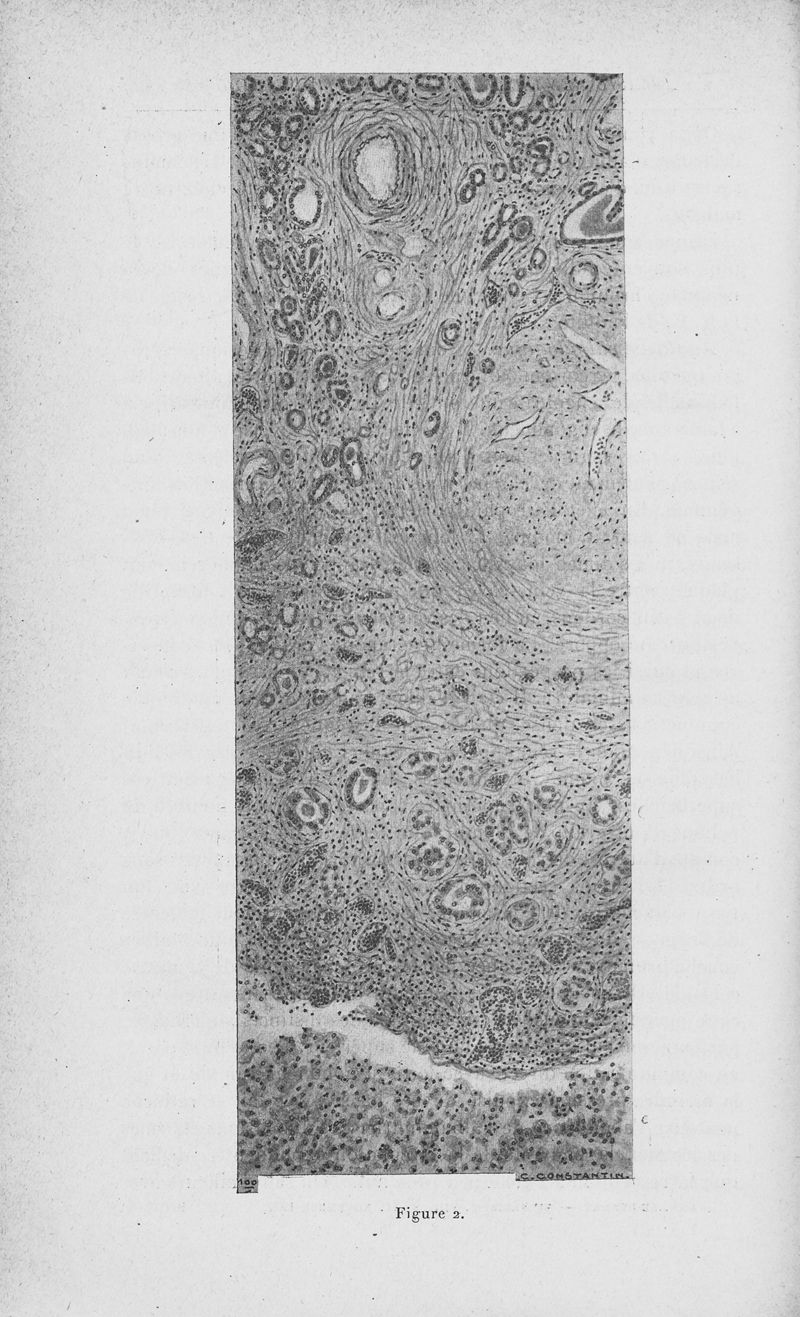

Annales de dermatologie et de syphiligraphie

6ème série, tome VIII. - Paris : Masson, 1927.